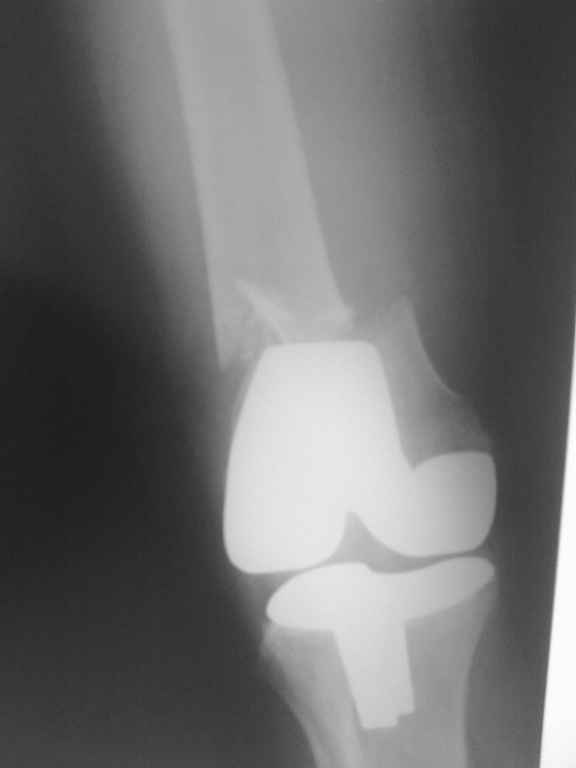

Поступила больная с перипротезным переломом

Перипротезный перелом у пациентки 67 лет . Эндопротезирование год назад . Сопутствующие нарушения ритма сердца и вес 120 кг при росте 185 .Думаю о мыщелковой пластинке с угловой стабильностью рыбинского исполнения остальное больной не потянуть . Заранее всем спасибо !